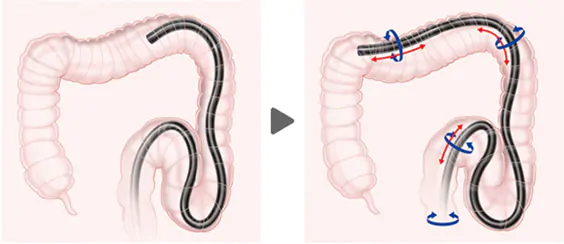

軸保持短縮法とは?

大腸は一見、一本の管のようですが検査を行う上では部位によって特徴が異なっています。それは、おおまかにいうと固定されている部分と固定されていない部分に分かれます。

大腸は一見、一本の管のようですが検査を行う上では部位によって特徴が異なっています。それは、おおまかにいうと固定されている部分と固定されていない部分に分かれます。

直腸、上行結腸、下行結腸は固定されていますが、S状結腸、横行結腸は固定されていません。

特にS状結腸はS状というだけあって、その名の通り、曲がりくねっていて、ぶらぶらの状態です。そのため内視鏡を押し込みながら挿入していくと、大腸が伸びてしまいます。大腸カメラが痛いという理由の大部分は、この腸が伸ばされることによって起こっているのです。

当院で行う軸保持短縮法とは、空気を極力入れず、腸管を伸ばさないように、その都度腸管を折りたたんで進めていく方法です。

例えると、ジャバラのホースを短くしながら、その中を進んでいくイメージです。技術的には内視鏡を進めては戻し、戻しては進めるといった感じで、少しずつ腸をたたんでいきます。それによって図のように直線的にカメラが進んでいきますので、痛みを最小限に抑えることができるのです。

もちろん、腸が長い方や体系や年齢によっても腸の状態は人それぞれです。腸の伸びやすい方には、お腹の上から手のひらで圧迫をして、体の外から腸が伸びるのを抑えます。

また体の向きを変えて、腸の曲がり角を緩やかなカーブにして、カメラが通りやすくしたりもします。軸保持短縮法では、最終的には1メートル以上ある大腸が70㎝程度で終点(盲腸)まで到達することができるのです。